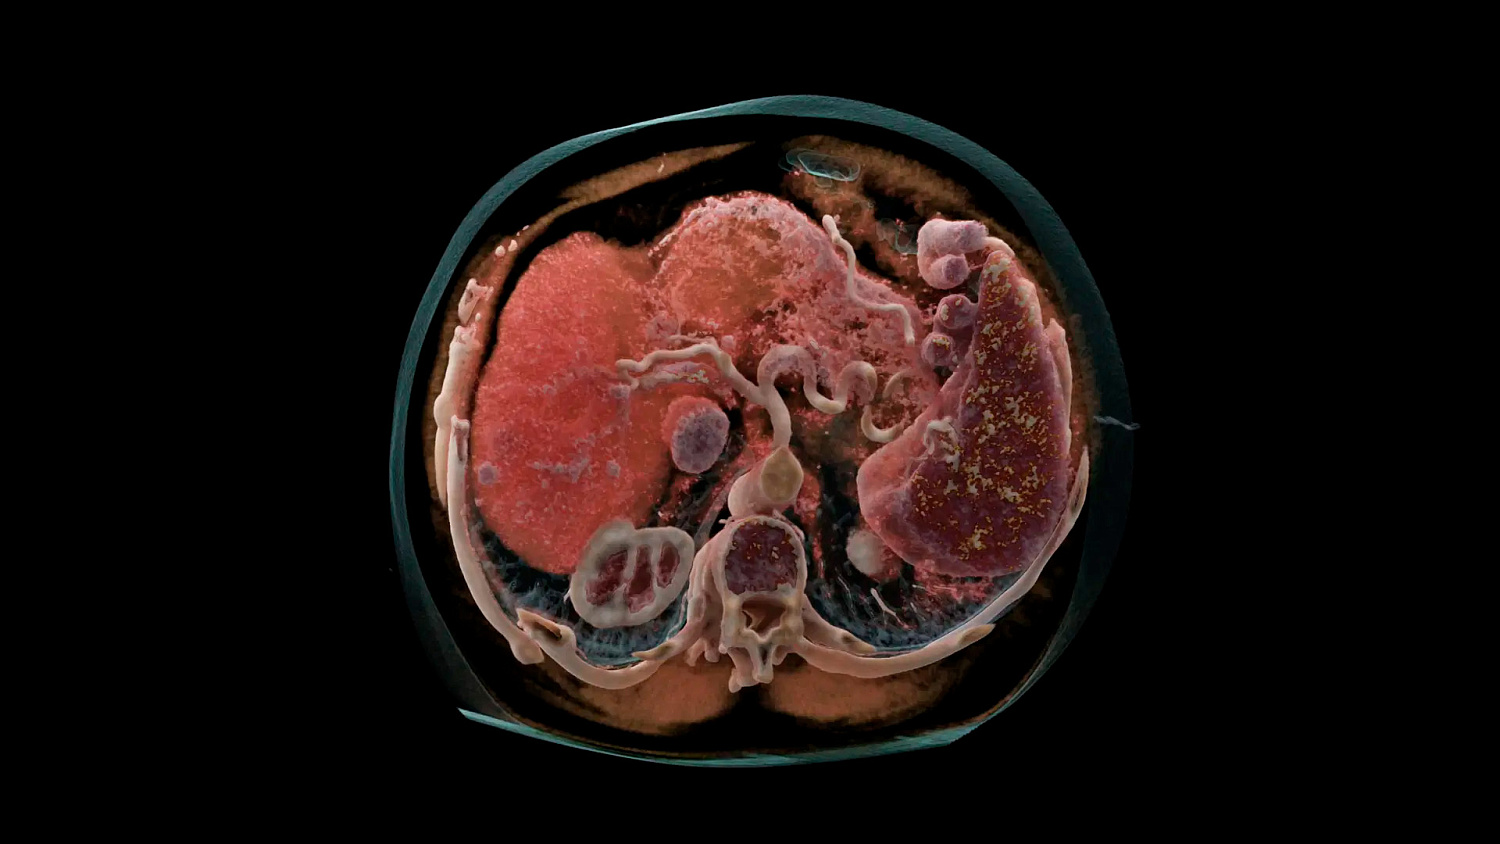

Квантовая спектральная визуализация

Получайте спектральные карты при каждом сканировании, независимо от скорости сканирования, поля обзора или пространственного разрешения. Это обеспечивает точную функциональную оценку без каких-либо компромиссов.

Квантовая итерационная реконструкция

Обеспечьте оптимальное качество изображения и снижение уровня шума с помощью итеративной реконструкции спектральных данных на основе моделей с полной синхронизацией между потоками данных и с высокой и низкой энергией.